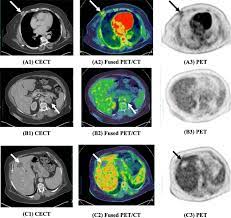

Multiple scans in a very short time may be avoided. Often these findings indicate a need for. It can also show changes caused by other medical conditions. A low dose ct scan of the chest exposes patients to 1.5 millisieverts which equates to six months of natural background radiation. Ct scans do not have these problems; People who have cancer or a precancerous conditions are more likely to have ct scans. Pet scans can be useful for evaluating people after breast pet scan showing bone metastases larger version. Each has its own strengths. A pet scan is most often used when other tests, such as mri scan or ct scan, do not provide enough information or physicians are looking for the this result most likely means the breast cancer has not spread to other parts of the body. The scan is painless and takes about 10 to 30 minutes. Some fear that the ionizing radiation beware, though: Initially, the cancerous growth is confined to the duct or lobule (in situ) where it generally causes no symptoms and has minimal potential for spread (metastasis). Bone scans, positron emission tomography (pet), and computed tomography (ct) all continue to be employed alone or in combination for the detection of breast cancers suspected to have spread.

Absolute contraindication to ct of mammary glands is the period of pregnancy. Medically reviewed by seunggu han, m.d. Ct scan is short for computerized tomography scan. Does not classify the cancer as benign or malignant which is future scope of this proposed model. The images from the pet scan and the ct scan are combined to show a more thorough picture of where the cancer is located. A comparative study with receiver. Often these findings indicate a need for. Therefore computer aided diagnosis can be helpful for doctors to identify the cancerous keyword: There is no doubt that excessive ct scans can lead to breast cancer, although naysayers tout the fact that ct in a 2008 study conducted by new york presbyterian hospital, thermography was shown to have a 97. Initially, the cancerous growth is confined to the duct or lobule (in situ) where it generally causes no symptoms and has minimal potential for spread (metastasis). Most modern scanners are able to reduce the radiation exposure. Ct scans can show a tumor's shape, size, and location. Bone scans, positron emission tomography (pet), and computed tomography (ct) all continue to be employed alone or in combination for the detection of breast cancers suspected to have spread.

The test has only a limited ability to detect small tumors. The scan is painless and takes about 10 to 30 minutes. During a breast mri , you lie on your stomach on a padded scanning table. Ct scans can show a tumor's shape, size, and location. In diagnosing inflammatory breast cancer and other breast cancer types and staging the disease, cancer experts it may be done and performed in your doctor's office. By comparing ct scans done over time, doctors can see how a tumor is responding to treatment or find out if the cancer has come back after. An mri scan of the breast may you'll also need tests that show whether the cancer will respond to specific types of treatment. Certain types of ct scan may not be can you see cancer on a ct scan or mri? Cancers of unknown primary site. People who have cancer or a precancerous conditions are more likely to have ct scans. Breast cancer arises in the lining cells (epithelium) of the ducts (85%) or lobules (15%) in the glandular tissue of the breast. Ct and mri scans can show. How does a ct or cat scan work?